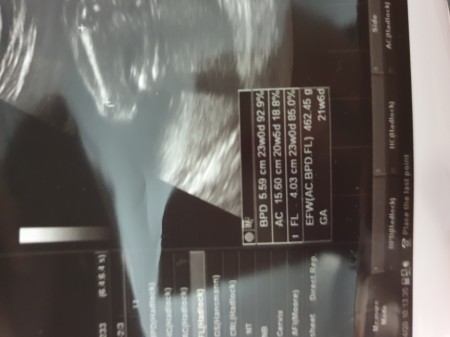

Ultrason Terimleri Hamilelikte Olcumler Crl Bpd Ne Demek Buyurken